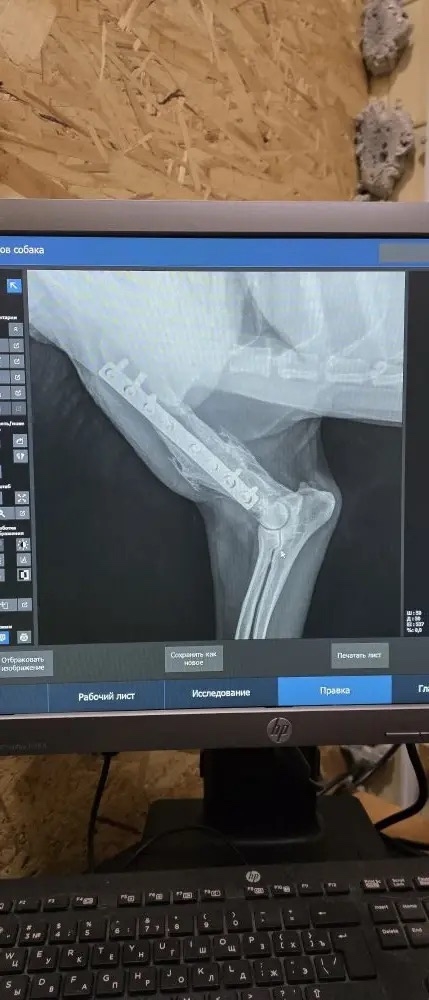

В ветклинике «Друг» сделали рентген, по снимку – свежего перелома нет, НО в области правой плечевой кости имеется металлоконструкция в виде пластины, видимо когда-то была травма/перелом и проведена серьезная операция, сейчас образовался свищ и небольшое нагноение в этом месте (причина не установлена), но врач предположила, что хозяин очень заботился о собаке и лечил ее, т.к. проведенная операция была сложная.